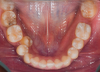

Fig 8. A class III adult male patient required surgical orthodontic treatment. The patient had anterior and posterior crossbites and required leveling of a deep curve of Spee during presurgical orthodontics.

Fig 9. A class III adult male patient required surgical orthodontic treatment. The patient had anterior and posterior crossbites and required leveling of a deep curve of Spee during presurgical orthodontics.

Fig 10. A class III adult male patient required surgical orthodontic treatment. The patient had anterior and posterior crossbites and required leveling of a deep curve of Spee during presurgical orthodontics.